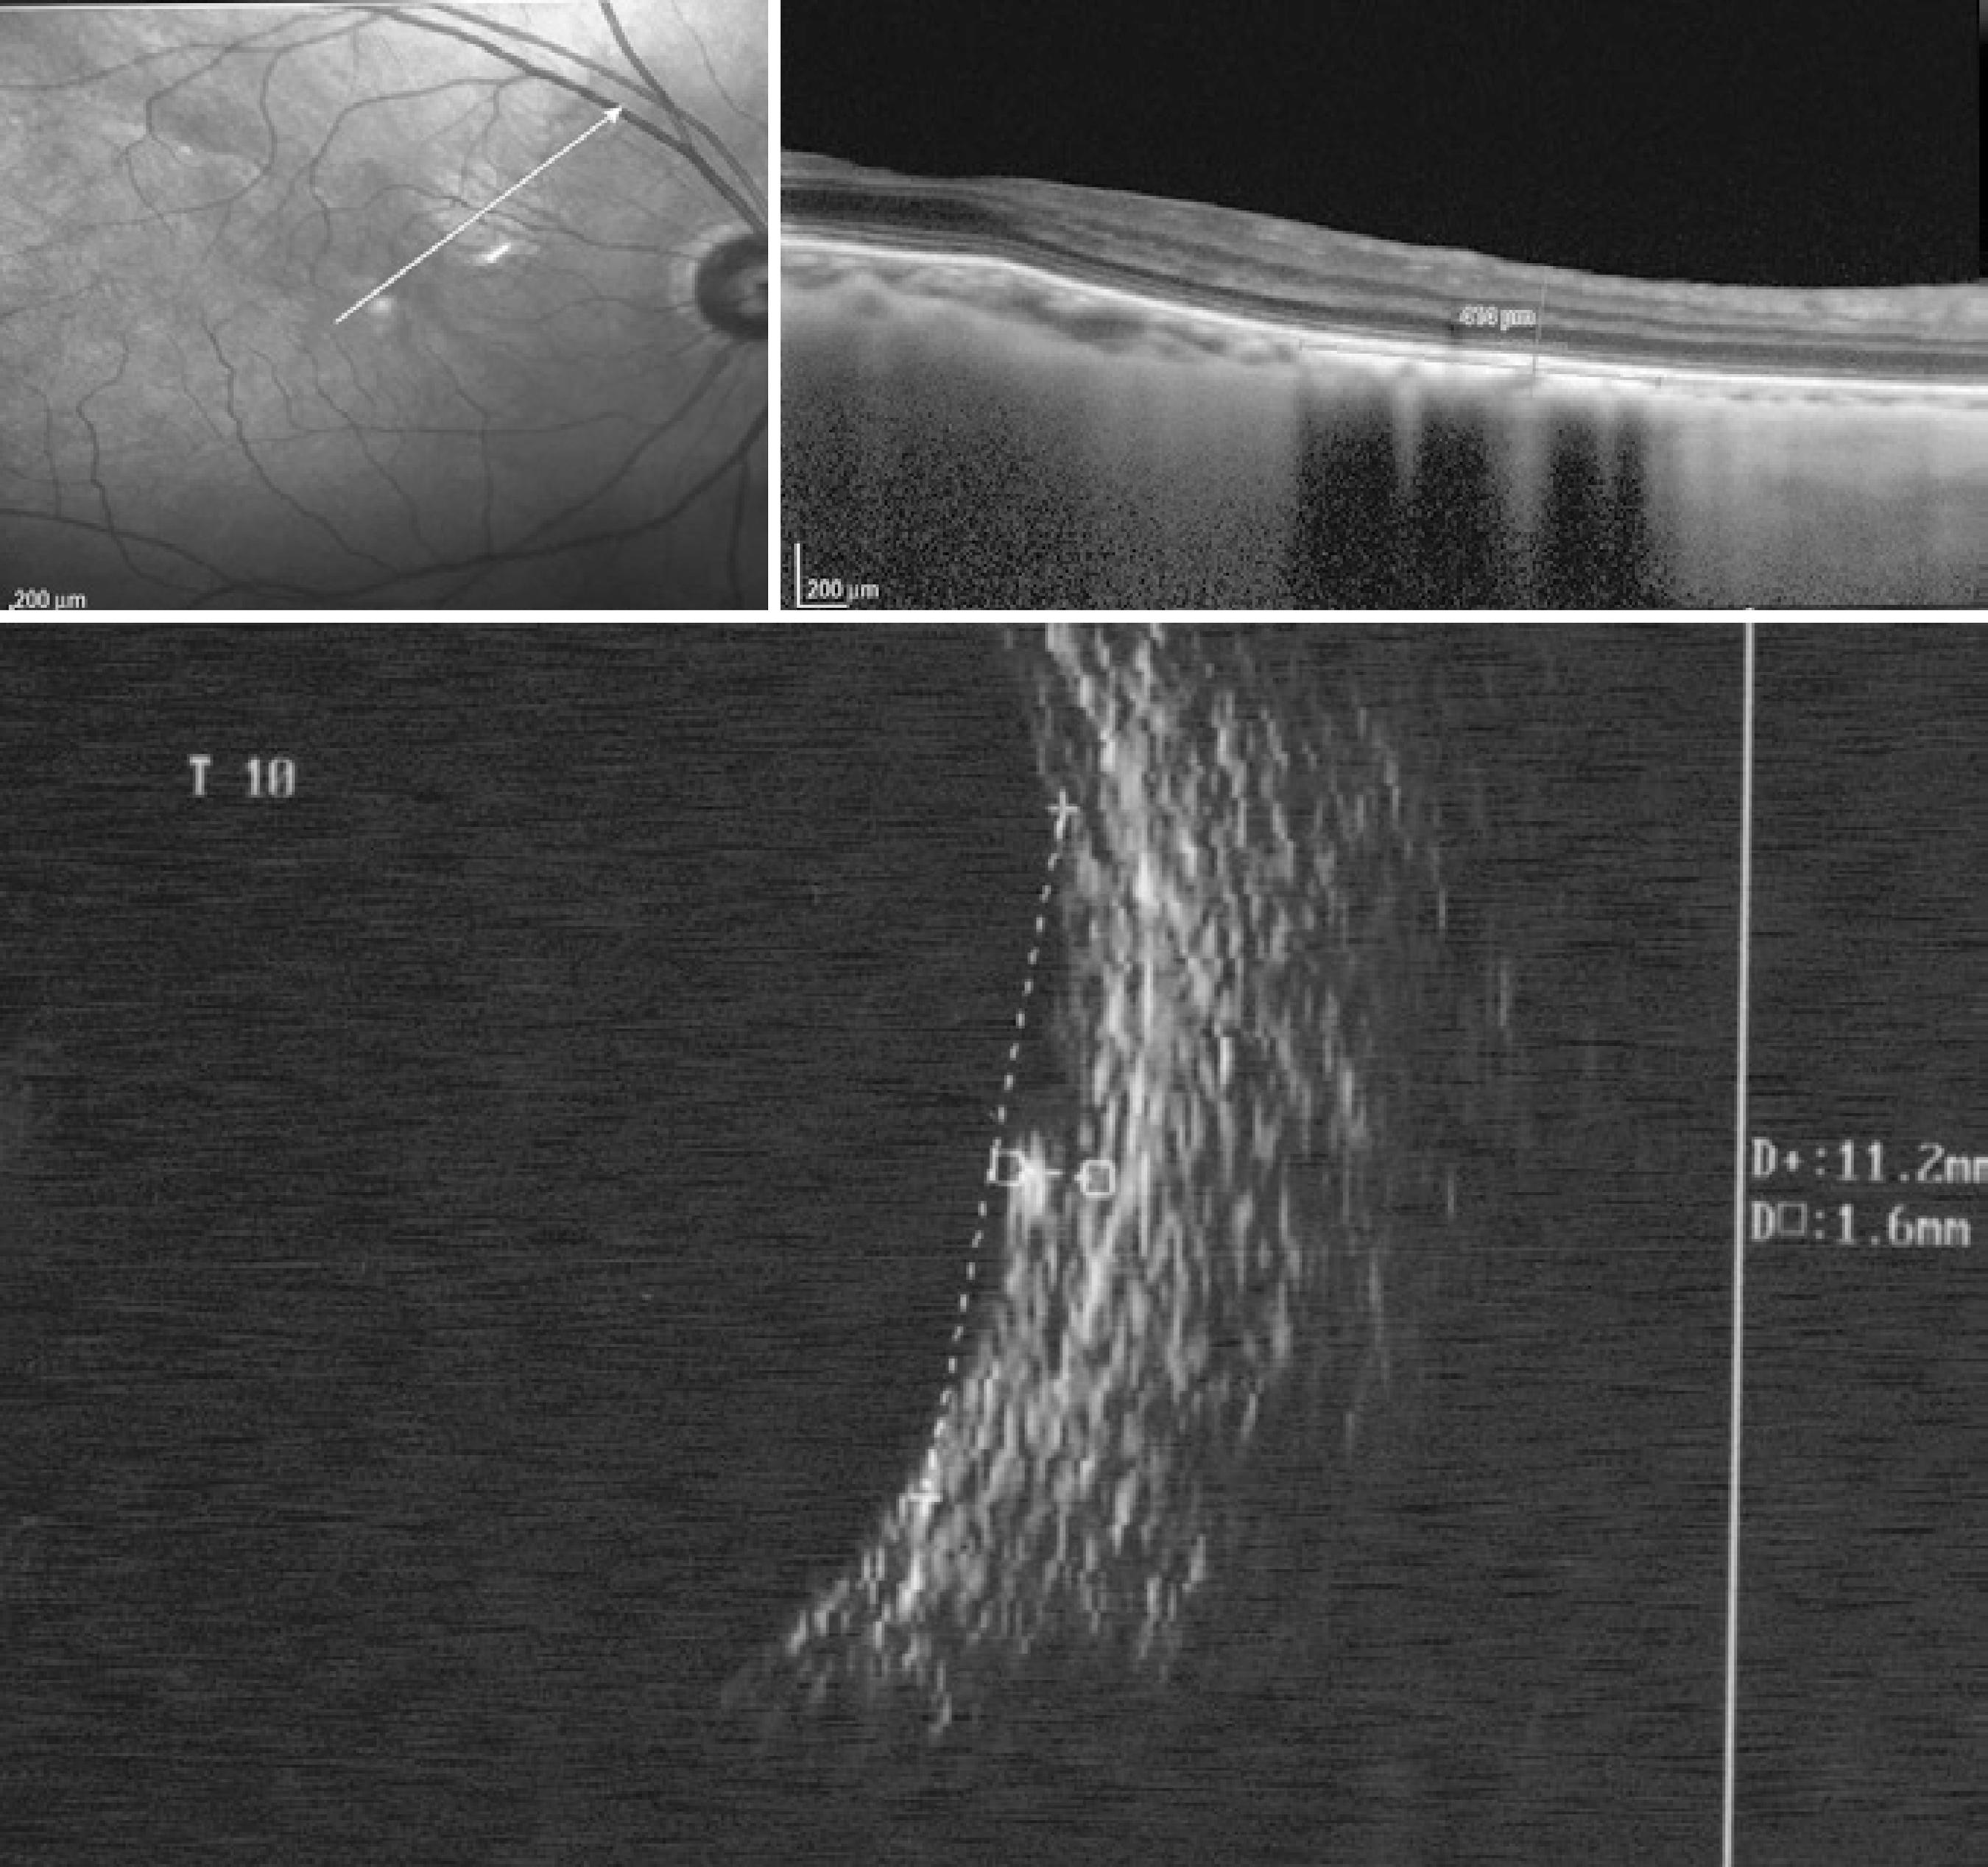

Measurements were obtained by both methods (US and OCT) in the same manner. The AP diameter was measured from the optic nerve toward the periphery, the transverse (T) basal diameter was acquired perpendicular to the AP, and height was measured between the internal limiting membrane and the top of the sclera. When it was impossible to see the sclera on OCT due to the shadow caused by the high internal reflectivity of the nevus, an imaginary line was drawn to join the images from the origin of the adjacent sclera, and this line was considered the posterior limit of the lesion (Figure 1).

Figure 1 Choroidal nevus located at the posterior pole. Anteroposterior diameter, 6.2 (20-MHZ ultrasound , lower left) and 5.59 mm (optical coherence tomography , top left); transverse diameter, 11.0 (20-MHZ US, lower right) and 6.12 mm (OCT, top right, dimension apparently undersized on OCT); height, 2.3 mm (20-MHZ US, lower right) and unfeasible to determine on OCT (top right) because the limit between the choroid and sclera was unclear. In the upper left image, OCT revealed the presence of subretinal fluid adjacent to the lesion

Height was the most difficult parameter to measure on OCT. For some choroidal nevi, it was possible to determine the origin of the sclera on OCT (Figure 2); however, in others, an imaginary line was drawn to join the images from the origin of the adjacent sclera, and this line was considered as the posterior limit of the lesion (Figure 1).

Figure 2 Choroidal nevus (case 14) located at the posterior pole and identified by spectral domain optical coherence tomography (0.41 mm in height) and a comparison with 20-MHz ultrasound (1.6 mm in height)

In our analysis, although no significant difference was observed between the measurements of the choroidal nevus using the 10- and 20-MHz transducers (p<0.05), when the AP and T diameters and height were compared, better resolution was achieved using the 20-MHz probe under direct contact, resulting in a better definition of the lesion limits (Figure 1).